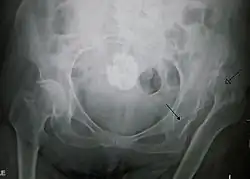

| X-ray showing a joint dislocation of the left hip. | |

An anterior-posterior (AP) X-ray of the pelvis and a cross-table lateral X-ray[24] of the effected hip are ordered for diagnosis.[4][5][16] The size of the head of the femur is then compared across both sides of the pelvis. The affected femoral head will appear larger if the dislocation is anterior, and smaller if posterior.[7] A CT scan may also be ordered to clarify the fracture pattern.[20]